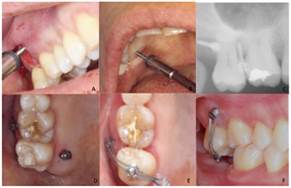

Inserción de los mini-implantes cuadrante I

Se infiltró articaína 4% con epinefrina 1:100000 en fondo de saco del 1.7 y 1.6 y palatino, posteriormente se realizó corticotomía en mesial del 1.7 con la técnica piezocisión descrita por Dibart12 (Fig. 3) posteriormente se realizaron las punciones en la zonas de inserción por medio de una sonda periodontal. Con el uso de un destornillador manual tamaño largo, fue colocado el mini-implante mesiovestibular y distopalatino. Una vez colocados, se tomó una radiografía periapical de control para verificar que los mini-implantes no dañaran las raíces de los dientes vecinos. Después se colocó un botón metálico en oclusal con la finalidad de evitar el desalojo de la cadena ortodóntica con la cual se realizaría la fuerza intrusiva (Fig.4).